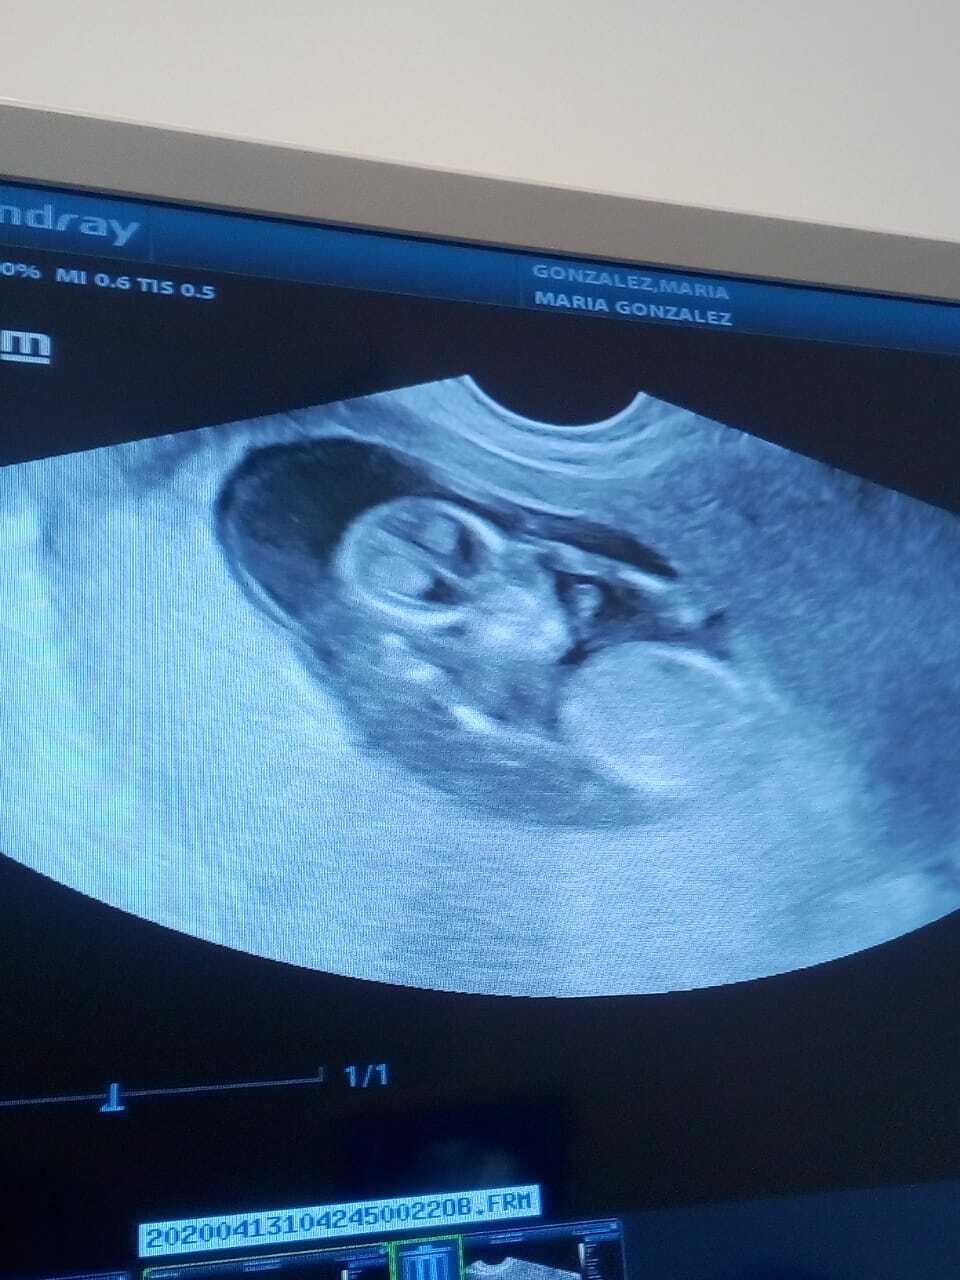

ULTRASON